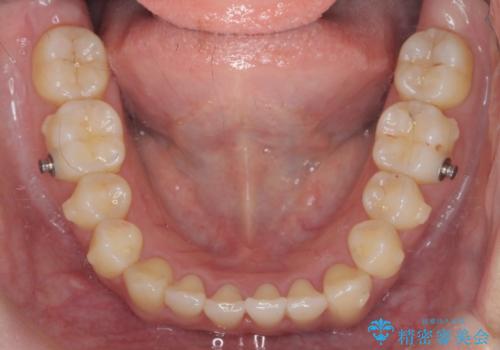

ワイヤー部分矯正治療を併用したマウスピース矯正治療

- 前歯のねじれ、深い噛み合わせ(ディープバイト)の改善を求めて来院されました。

マウスピースでは改善の難しい、歯のねじれ・ディープバイトを部分ワイヤー矯正で改善したのち、マウスピース矯正で全体の歯並びを整えていきます。

部分ワイヤー矯正を行ったことで前歯をしっかりと綺麗な歯並びへと導くことができました。